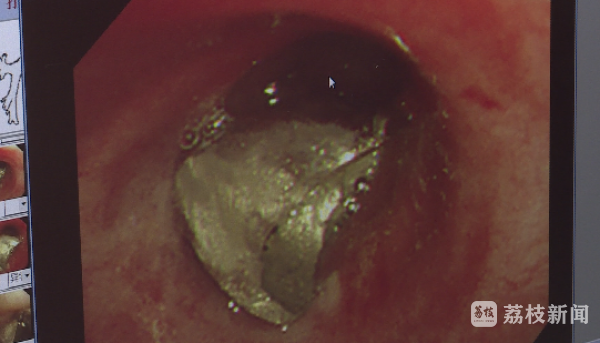

当天,张先生听从医生的建议,紧急转诊到镇江市第一人民医院进行进一步检查,确诊了他的左主支气管有一枚长度约1.2厘米的假牙,需立即手术处理。

摸清情况后,丁主任立即为张先生进行了气管镜介入手术,通过气管镜确定喉内具体情况,精准定位到假牙,再用钳子一气呵成取出,整个手术只用了10分钟。

丁浩介绍,“这种牙托都是打磨过的,边缘特别光整,所以我们就用异物钳活检了之后把它拽出来了。”